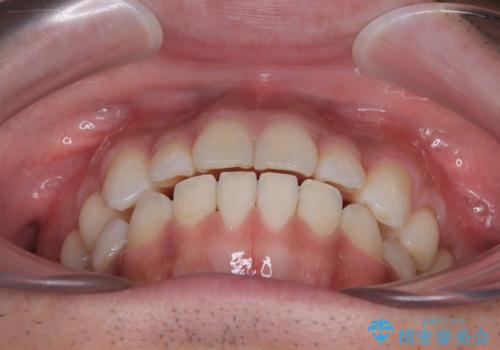

目立たない装置でデコボコを改善 ハーフリンガルによる矯正治療

一年と数か月で矯正を終えることができました。

下顎前歯部には後戻り防止のワイヤーを装着しています。